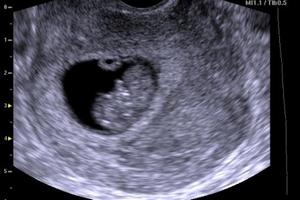

У дитини вже появились зачатки всіх органів і систем, зараз йде їх остаточне формування. Плацента ще формується, ворсинки трофобласта розгалужуються все більше і проникають все глибше. Від того як пройде цей процес, залежить все подальше внутрішньоутробне життя дитини, адже саме плацента буде єдиним постачальником кисню і поживних речовин довгі місяці до пологів. Шкіра дитини стає все досконаліше. Хоча вона зараз майже прозора, на долоньках вже з'явилися потові залози, правда, вони поки не функціонують. А ось сальні залози розвинені і функціонують не гірше ніж у дорослих, поступово накопичуючи на шкірі дитини шар мастила.

Личко сформувалося, хоча очі зміщені дуже широко, практично до скронь. Зорові нерви розвинулися, практично сформувалася сітківка очей, а з зовнішніх покривів утворюється рогівка і кришталики. У малюка вже формуються повіки. Щелепи дитини знайшли нормальну форму, і в них уже утворюються зачатки молочних зубів, видно верхню губу. У роті вже є добре сформований язик з смаковими рецепторами. Ніс знаходить звичний вид, в його порожнини утворюються цибулини нюхових нервів. Тільки відчути дитина поки нічого не може, носові ходи щільно перекриті слизовими пробками.

Зараз головний дихальний орган не легені, а плацента. Кишечник подовжився, утворює безліч петель і робить в черевній порожнині поворот навколо своєї осі, при цьому процесі йому мало місця в черевній порожнині, і він частково знаходиться в пупковому канатику (фізіологічна ембріональна грижа). Такий стан речей є нормальним ще протягом місяця, після чого кишечник повернеться в черевну порожнину. Почалося формування статі плоду. У хлопчиків йде закладка яєчок, у дівчаток яєчників. Цікаво, що якщо ви носите дівчинку, у неї зараз генеруються яйцеклітини, які потім будуть витрачатися все її життя. Саме зараз закладаються основи здоров'я ваших онуків.

По виду промежини ідентифікувати стать поки не можливо, статевий горбок виглядає однаково у хлопчиків і у дівчаток.

Животик і раніше не помітний, хоча ваша матка вже збільшилася і зараз досягає розмірів невеликого апельсина. І ви вже можете почати відчувати, що потрібно більш вільний одяг, так як живіт став трохи об'ємніший.